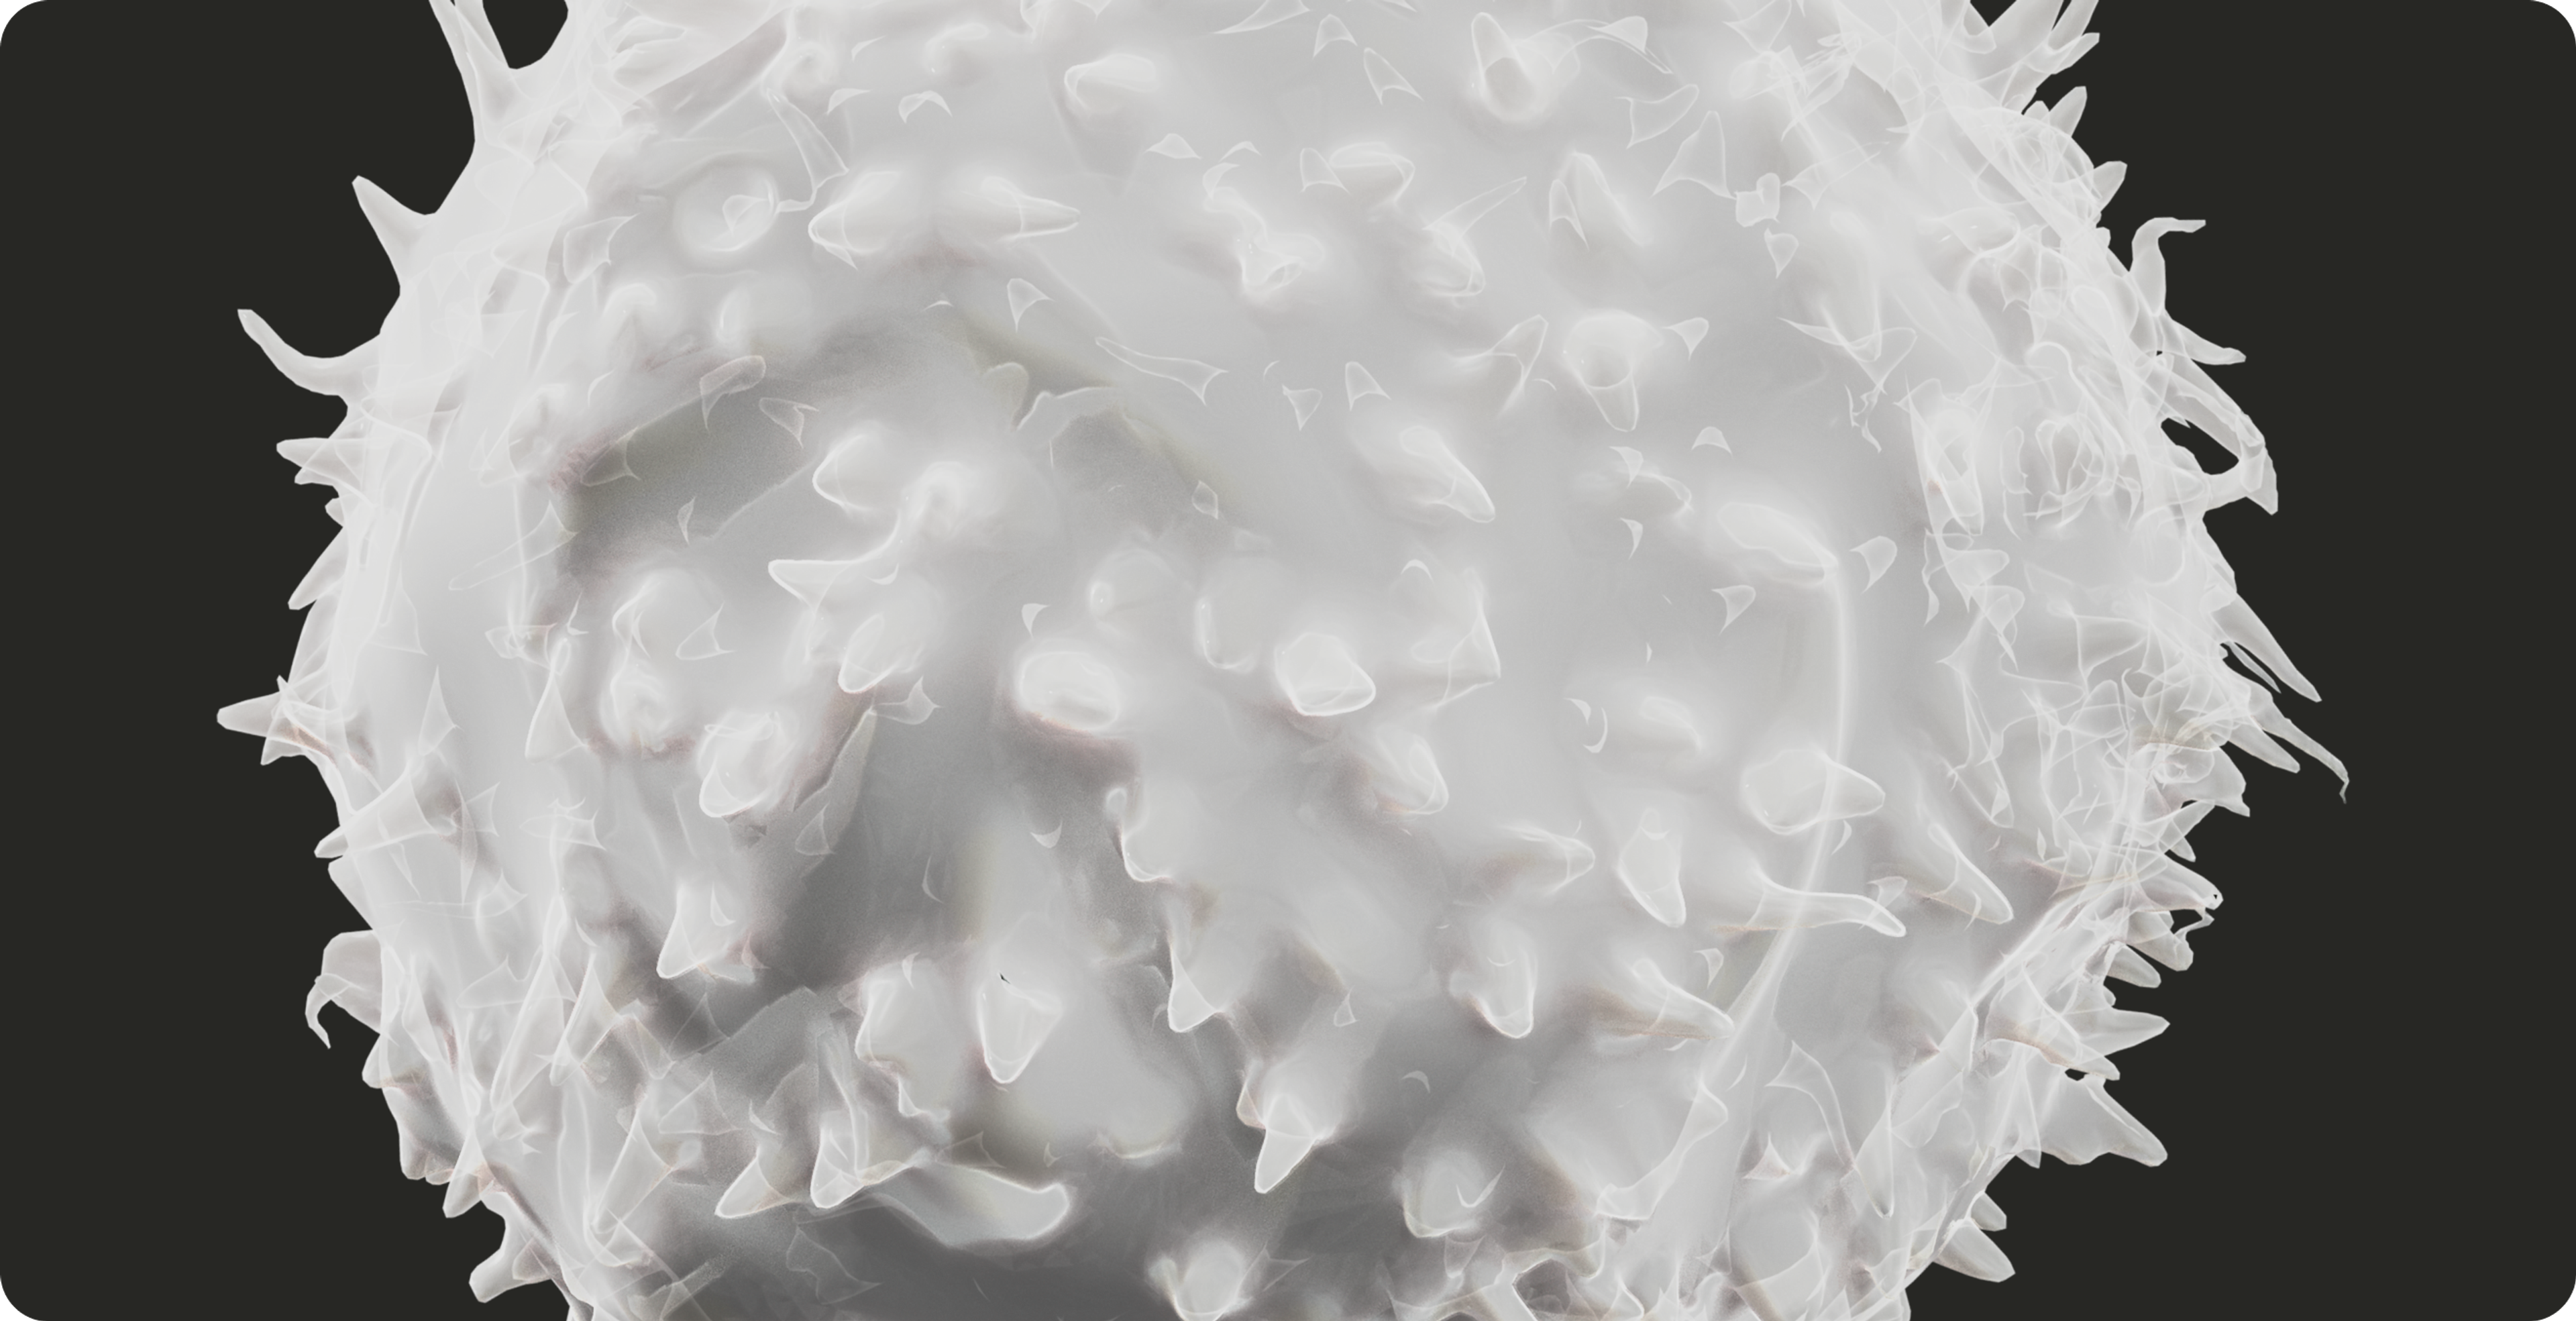

2. Mitochondria and Immune System Regulation

Our immune system relies on energy from our mitochondria, and mitochondrial dysfunction plays a role in an aging immune system. However, the mitochondria play an active role in our immune response outside of energy production.

Innate immunity

Our innate immune system is our body’s first line of defense against invaders and pathogens. It provides a rapid but non-specific response.

When damaged, the mitochondria send out warning signals, activating immune pathways and starting the inflammatory process.

Even if the immune response starts outside the mitochondria, they can act as a guide, shaping how the immune cell will respond to the foreign invader.[7]

Adaptive immunity

Our adaptive immune system is a highly specific and targeted immune response that remembers foreign substances for the next time they are encountered.

During an immune response, the mitochondria support the production of immune signaling molecules like IL-2 (interleukin-2). Additionally, mitochondria can shape-shift, divide, and fuse together to regulate the metabolic demands required for immune cells to function.[8]

This behavior helps to determine if an immune cell goes into “attack mode” or stays in a memory state (long-term immunity).

Mitochondria recognize viruses

Surprisingly, the mitochondria can recognize when a virus has entered a cell, activating a protein that lies in the outer member of the mitochondria. This protein helps to amplify the cellular alarm signal, mounting an immune response, and halting further spread of the virus.[9]

Regulators of inflammation

Mitochondria play a key role in regulating inflammation, acting as both initiators and modulators of the body’s immune response. When cells experience stress, infection, or damage, mitochondria release signals such as mitochondrial DNA (mtDNA) and reactive oxygen species (ROS). These molecules act as danger signals, activating inflammatory pathways that help the immune system respond to threats.[10]